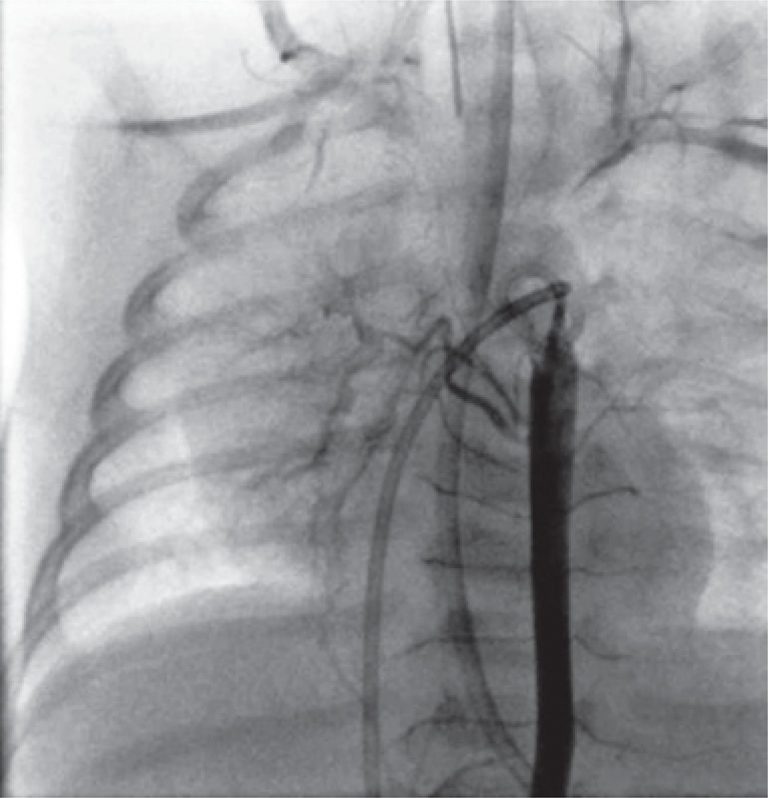

Na ecocardiografia transtorácica, o coração estava normal, em termos estruturais a funcionais. Porém, a artéria pulmonar direita não estava bem evidente. Foi realizada uma angiotomografia para esclarecer este achado, mas o resultado foi inconclusivo. Foram excluídos os diagnósticos de hemitruncus e persistência do canal arterial. Em seguida, foi submetido a cateterismo, e a angiografia pulmonar revelou agenesia da artéria pulmonar direita (), excluindo ramos ocultos da artéria pulmonar. O pulmão direito era perfundido pela árvore brônquica () e não foram encontradas outras anomalias.